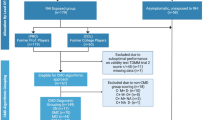

We evaluated cognitive performances and magnetic resonance imaging findings in 20 American football players enrolled according to the following inclusion criteria:

We divided the football players into 3 groups according to their field position (type 1, 2 or 3 — see below) and into two groups according to their career length (≤ 7 or > 7, i.e., the median of career length observed in our athletes). Field positions were categorized as follows:

For the neuroimaging study, we recruited a control group of healthy males without TBI history and without major neurological or systemic pathologies, matched by age.

The study was carried out according to the ethical principles of the Helsinki Declaration for medical research. The subjects expressed their written consent to participate in the study.

The demographic characteristics of the American football players are showed in Table 1. The 19 male healthy controls were age-matched with the players, with a median [25th–75th percentile] age of 28.0 [24.8–32.3] years (p = 0.235).